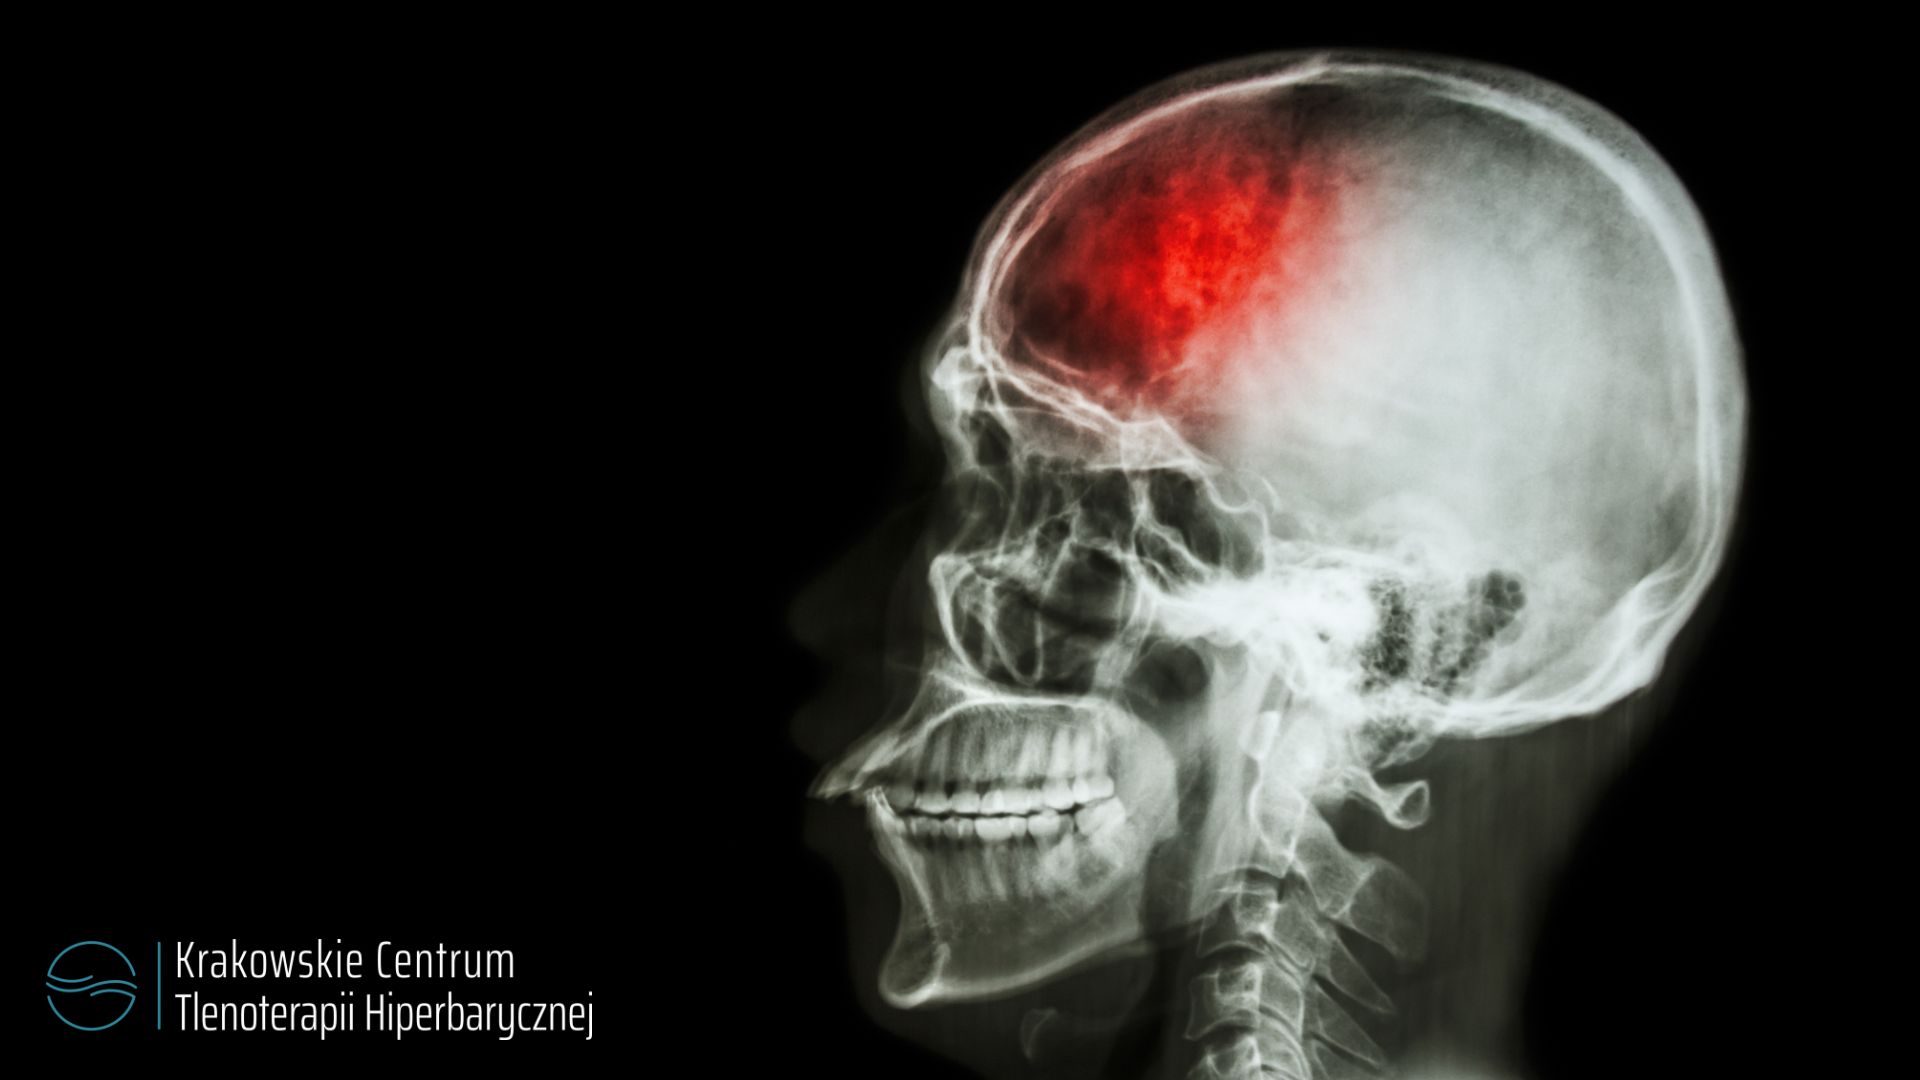

Prowadzone w świecie badania, m.in. przez ośrodek prof. Efratiego, wykazały pozytywny wpływ hiperbarii w leczeniu skutków udaru mózgu. Wiadomo, że specjaliści z Izraela wykonywali neurobrazowanie, oceniając jakie zmiany zachodzą w mózgu przed zabiegiem i tuż po. Wyraźnie wykazano, że terapia tlenem o podwyższonym ciśnieniu zmniejsza obrzęk mózgu, poprawia przepływ tlenu i komunikację neuronów. Regenerują się nawet te obszary, które są nieaktywne (zniszczone).

Terapia w komorze po świeżo przebytym udarze jest niewskazana – są bowiem problemy z uregulowaniem ciśnienia pacjentowi, dlatego nie wolno dokładać czynnika, który mógłby to zaburzać. W późniejszym etapie nieodzowna jest bardzo dobra kwalifikacja chorych. W przypadku udaru chorzy muszą być doskonale przebadani – konieczne jest badanie neuropsychologiczne, neurologiczne. Tlen nie tylko przynosi pozytywne skutki, ale może wywołać np. napad padaczki u osoby o szczególnej wrażliwości. Dlatego kwalifikacja do leczenia tlenem jest taka ważna. Do leczenia w komorze wskazaniem jest też encefalopatia czy uszkodzenie spowodowane niedotlenieniem mózgu, na przykład po operacjach kardiochirurgicznych i innych, gdzie doszło do niedotlenienia.